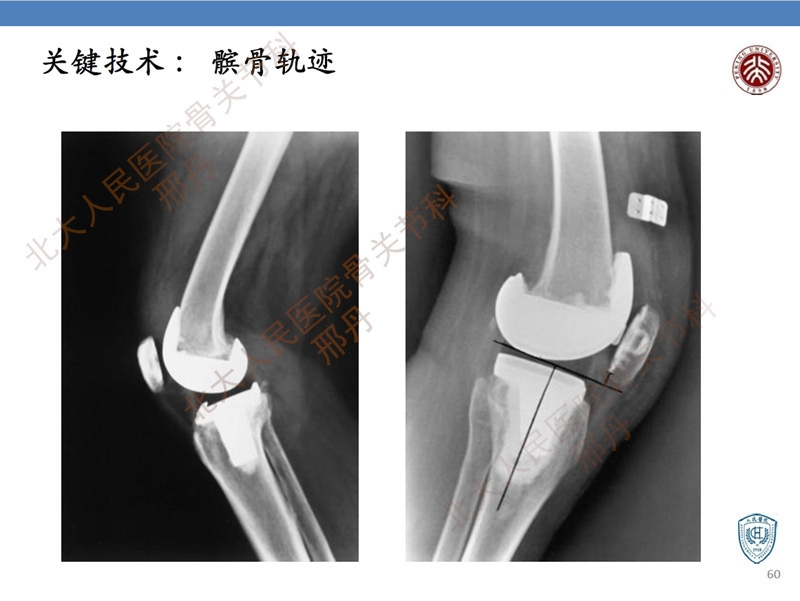

CR与PS假体的选择一直是关节外科医生关注的焦点之一,因为假体类型不同,对应的手术技术也不同。笔者认为,CR与PS全膝关节置换是两种不同的手术理念。然而,目前假体的选择依据尚待进一步探究,因此,手术医生必须了解假体选择的依据,同时更应该清楚不同假体对应的不同手术技术与细节。

本篇文章从疗效、假体生存率以及生物力学等方面介绍了CR与PS假体选择的依据。基于此,进一步讲述了不同假体对应的手术技巧。希望通过本文的讲授,帮助临床医生客观认识假体类型的决策原则,并掌握基本手术技巧。